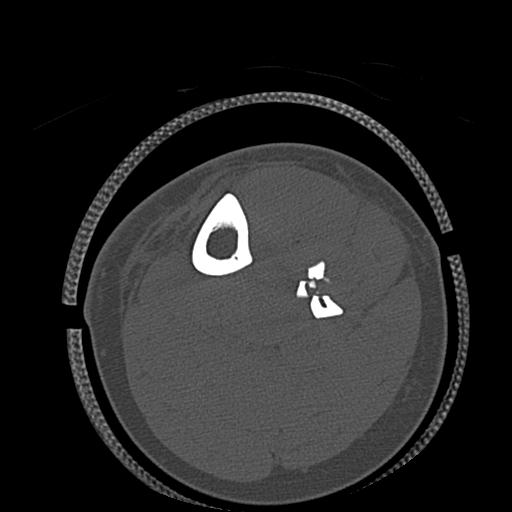

56476 8/28 4R 1/21 2R 左足関節 デジカメ写真 72歳女性 右足関節AS